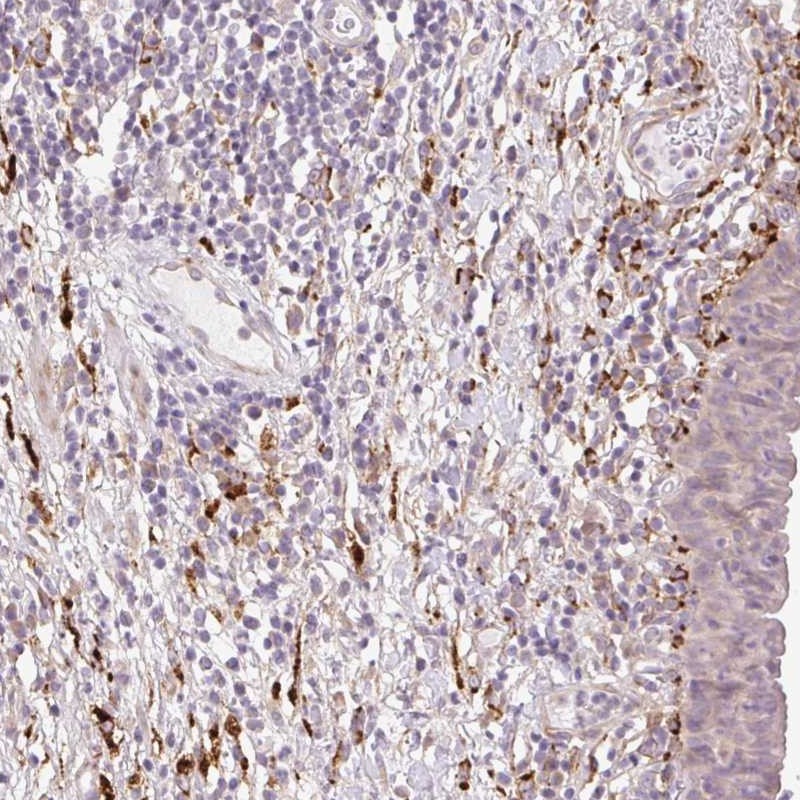

Immunohistochemical staining of human urinary bladder shows distinct positivity positivity in connective tissue.